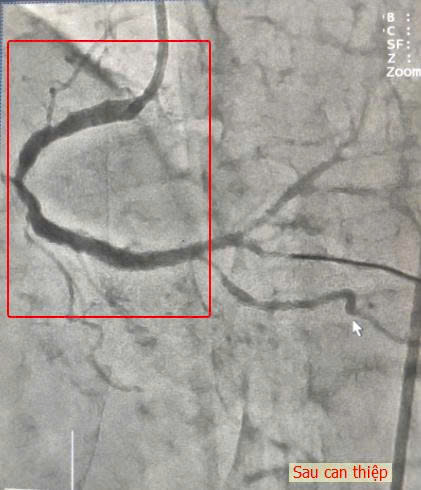

Nhận định mức độ nguy kịch, ekip Can thiệp Tim mạch lập tức tiến hành tái thông mạch vành khẩn. Thủ thuật được thực hiện nhanh chóng và chính xác, stent được đặt thành công, dòng chảy mạch máu phục hồi tối ưu. Toàn bộ quá trình diễn ra an toàn, không ghi nhận biến chứng.

Sau can thiệp, cụ bà giảm đau ngực rõ, được chuyển ICU theo dõi. Chỉ 24 giờ sau, huyết động cải thiện và cụ được chuyển về Khoa Nội Tim mạch – Can thiệp Tim mạch điều trị tiếp tục. Cụ K. hồi phục ổn định và xuất viện sau 7 ngày.

Hình ảnh sau can thiệp đặt stent